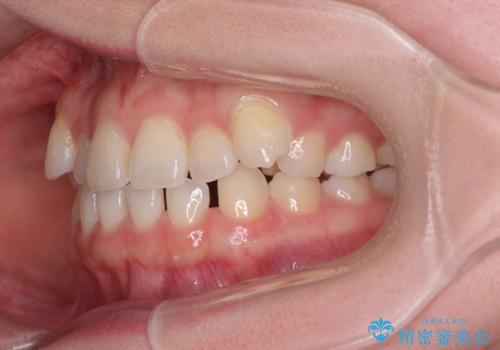

- 八重歯を気にして来院された患者様です。

口腔内の状況を確認したところ、左右ともに下顎第二大臼歯が欠損しており、咬み合うべき上顎の第二大臼歯が著しく挺出していました。

挺出した大臼歯を元の位置に戻すことは現実的に難しいため抜歯することとし、補助装置とワイヤー装置により上顎歯列全体を後方に移動することとしました。

順調に後方移動することができ、わずか1年強で治療を終えることができました。